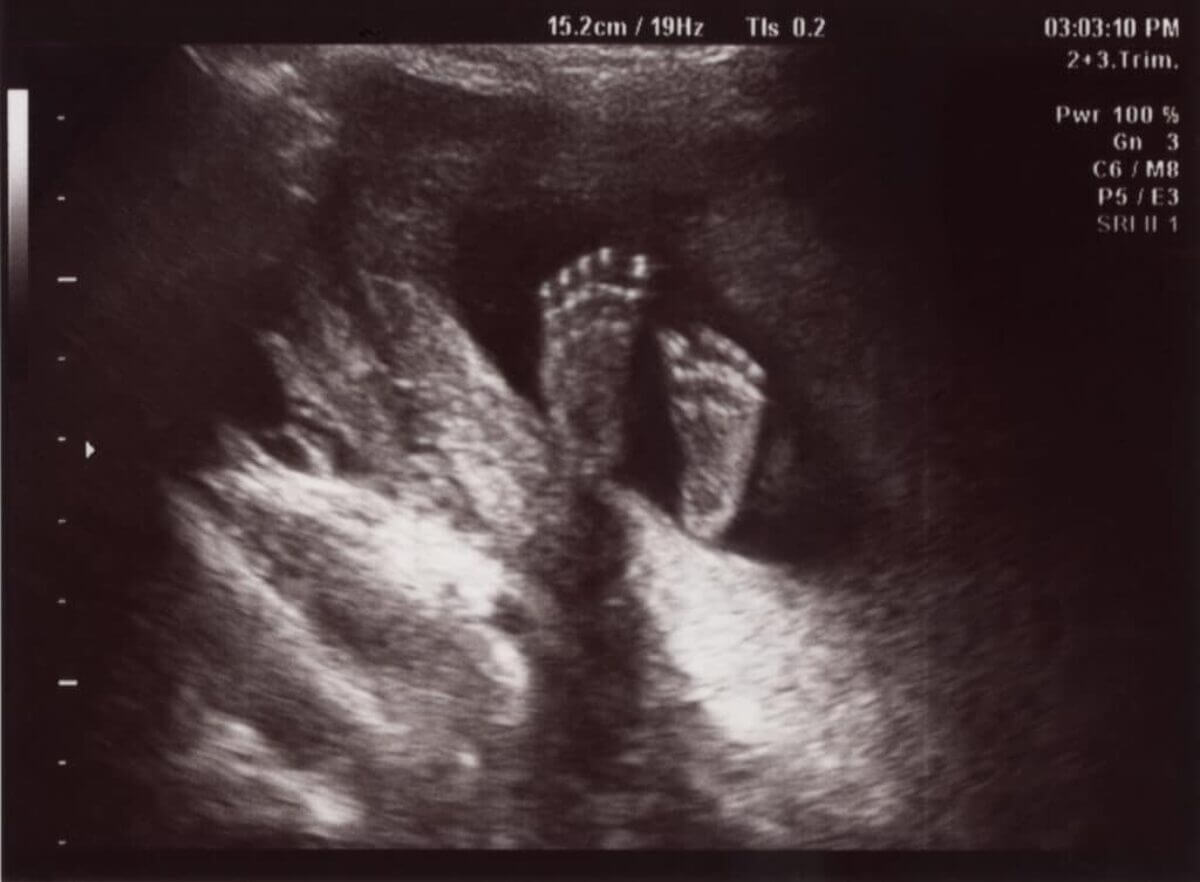

Most ultrasounds create flat (or two-dimensional) images. Some maternal and fetal medicine providers offer 3D or 4D ultrasounds. Both 3D and 4D ultrasound provide a more lifelike-appearing view of your baby inside the womb. 4D ultrasound provides live motion. It shows the real-time movement of your baby (like watching a movie).